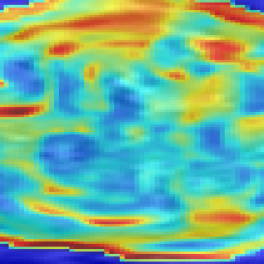

The evaluation of the reconstruction quality of a whole 3D image into a single-valued metric may not properly reflect the performance differences, as it is based on averaging values of all the pixels of all the input stacks. Furthermore, Tab. I indicates significant differences between variants of PVR but these differences have only minimal qualitative effect on reconstruction accuracy. Therefore, Fig. 12 evaluates the reconstruction quality of PVR additionally using dissimilarity heat maps based on the measured DSSIM (see Sec. IV-A). This approach allows further qualitative evaluation and allows for uncertainty visualization of PVR reconstructions.

PVR surpasses the state-of-the-art SVR method especially for considerable non-rigid deformations. We have evaluated different variants of PVR using fixed-size and multi-size square patches and fixed-size and multi-size superpixels. ANOVA analysis has shown significant differenced between these approaches for different areas of the uterus. However, evaluation of motion compensation methods is difficult especially due to the lack of ground truth in fetal MRI. Mapping the reconstruction quality of a whole 3D volume into a single-valued metric may not properly reflect qualitative differences, as it is based on averaging all measured values of all the input stacks. Therefore, we have performed extensive qualitative analysis and present several examples and evaluation based on structural dissimilarity (DSSIM) heat maps.